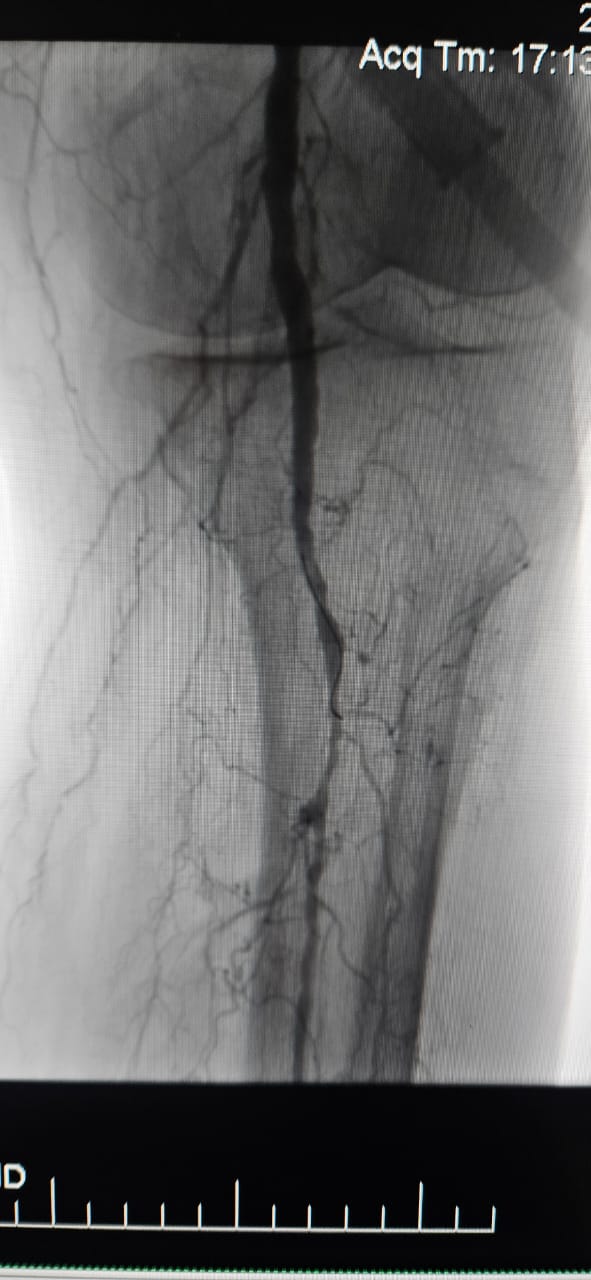

Temos o prazer de compartilhar um caso de sucesso de um hospital em Batumi, Geórgia, onde uma paciente de 78 anos com Isquemia Crítica do Membro (CLI) causada por oclusão total crônica da artéria do membro inferior apresentou notável melhora clínica após o tratamento com o Sistema de Dilatação de Balões Periféricos ThorCrack IVL.

Este caso ressalta o valor clínico da litotripsia intravascular (IVL) no tratamento de casos complexos de CLI com oclusão crônica de segmento longo-particularmente em pacientes com calcificação pesada, onde balões tradicionais ou dispositivos de aterectomia podem ter eficácia limitada.

Estamos orgulhosos de ver ThorCrack IVL capacitar médicos em todo o mundo para superar lesões calcificadas, restaurar a perfusão e melhorar os resultados dos pacientes na doença arterial periférica complexa.